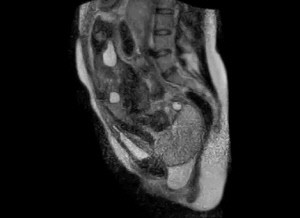

태아가 분만을 거쳐 태어나는 순간을 담은 MRI(자기 공명 영상법) 동영상이 공개돼 관심을 끌고 있다.

ABC뉴스는 독일 베를린 샤리테(Charite) 의과대학 전문의들이 세계 최초로 촬영한 MRI 영상 장면을 공개했다고 지난 26일(현지시간) 보도했다.

지난 2010년 일부 사진들이 공개 됐었지만 실시간 영상이 공개된 것은 이번이 처음이다.

다른 촬영기기와 비교해 방사선 피해 위험이 없는 것으로 알려진 MRI가 산모와 태아의 안전을 위해 사용됐다.

영상을 통해 태아의 위치를 정확히 파악해 산모의 분만을 효과적으로 도울 수 있기 때문이다. 제왕절개술이 필요할 경우에는 적절한 수술 시점을 결정하는 데 이번 영상이 유용하게 쓰일 것으로 보인다.